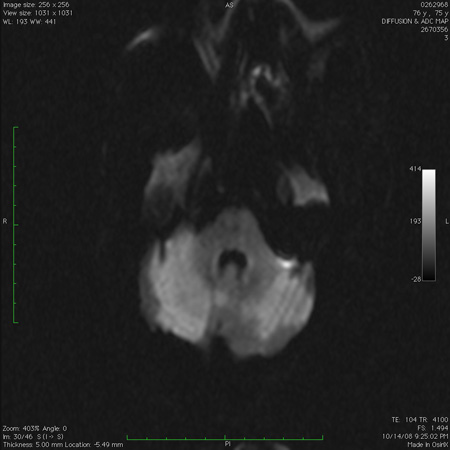

ნათხემის მწვავე ორმხრივი ინფარქტი დიფუზურ-შეწონილი მაგნიტურ-რეზონანსული ტომოგრაფიით

ექიმი ს.ჰ. საბრამონის კოლექციიდან; გამოყენებულია მფლობელის ნებართვით